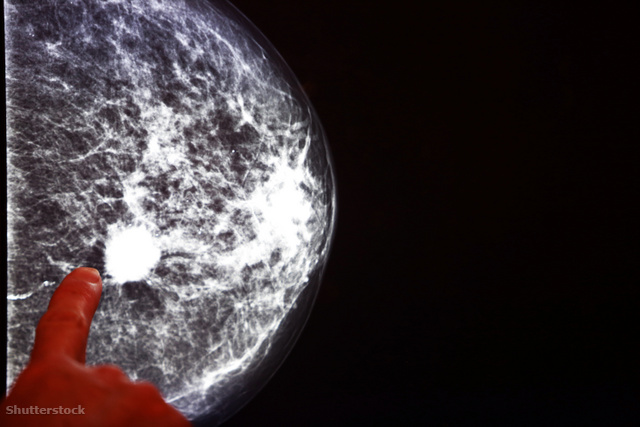

Szerencsére a mellrák manapság már nem egyenlő a halálos ítélettel, mert ha időben elcsípik, akkor számos beavatkozási lehetőség áll rendelkezésre. Ez pedig alapvetően a mammográfiás szűrővizsgálatnak köszönhető, mely becslések szerint csak az Egyesült Államokban nagyjából félmillió nő életét mentette meg.

Az első, mellet vizsgáló képalkotó eljárásokat az 1960-as években fejlesztették, 1989 óta pedig széles körben elérhető a mammográfiás vizsgálat, mely a mellrák diagnosztizálásának leghatékonyabb módja a 40 feletti nők esetében. Ha ugyanis még elterjedés előtt felismerik, akkor az ötéves túlélési arány 99 százalék, írja a ScienceAlert.

Egyértelmű tehát a mammográfia kiemelt jelentősége, de hogy ezt számszerűsítsék, a Colorado Egyetem kutatói megvizsgálták, hogy pontosan milyen hatása volt az amerikai nőkre a vizsgálat elterjedése. Megállapították, hogy az elmúlt 30 évben 384 ezer és 614 ezer között lehet azoknak az amerikai nőknek a száma, akiknél diagnosztizálták a betegséget, és még időben sikerült közbeavatkozni. Körülbelül félmillió nő csak az Egyesült Államokban, globálisan tehát ennél jóval magasabb a szám.

Magyarországon az emlőrák a leggyakoribb ráktípus a nők körében. Évente nagyjából 7500 új esetet diagnosztizálnak, és körülbelül 2000 nő halálát okozza. A magyar nőket 45 és 65 év között kétévente behívják mammográfiás vizsgálatra, de alapvetően nagyon nagy jelentősége van a havi önvizsgálatnak, főleg a 45 év alatti korosztály esetében.